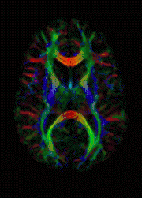

Diffusion tensor DTI Mainly tractography (pictured) by an overall greater Brownian motion of water molecules in the directions of nerve fibers.[21]

DTI image

Diffusion MRI measures the diffusion of water molecules in biological tissues.[41] Clinically, diffusion MRI is useful for the diagnoses of conditions (e.g., stroke) or neurological disorders (e.g., multiple sclerosis), and helps better understand the connectivity of white matter axons in the central nervous system.[42] In an isotropic medium (inside a glass of water for example), water molecules naturally move randomly according to turbulence and Brownian motion. In biological tissues however, where the Reynolds number is low enough for laminar flow, the diffusion may be anisotropic. For example, a molecule inside the axon of a neuron has a low probability of crossing the myelin membrane. Therefore, the molecule moves principally along the axis of the neural fiber. If it is known that molecules in a particular voxel diffuse principally in one direction, the assumption can be made that the majority of the fibers in this area are parallel to that direction.

The recent development of diffusion tensor imaging (DTI)[43] enables diffusion to be measured in multiple directions, and the fractional anisotropy in each direction to be calculated for each voxel. This enables researchers to make brain maps of fiber directions to examine the connectivity of different regions in the brain (using tractography) or to examine areas of neural degeneration and demyelination in diseases like multiple sclerosis.